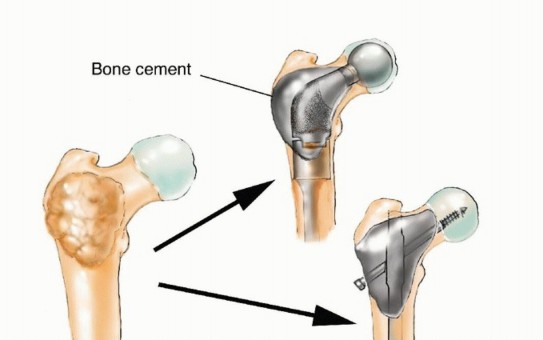

قد يحتاج المرضى المصابون بـ MBD إلى تدخل جراحي لإدارة كسر مرضي وشيك أو موجود بالفعل، أو لتخفيف الألم الشديد المرتبط بآفة متقدمة محليًا لم تستجب للعلاجات الأخرى. هذه "الأزمات الهيكلية" تؤدي إلى فقدان كبير في الوظيفة، وألم، وتدهور في جودة الحياة. في حالات نادرة، قد تُجرى الجراحة لإزالة ورم نقيلي عظمي وحيد بهدف تحسين البقاء على قيد الحياة على المدى الطويل لمرضى مختارين. ومع ذلك، فإن معظم التدخلات الجراحية تكون تلطيفية في المقام الأول، وتهدف إلى التحكم الموضعي في الورم، وتوفير الاستقرار الهيكلي للموقع المعالج جراحيًا، واستعادة الوظيفة الطبيعية بأسرع وقت ممكن.

يُعد الفشل في تحقيق هذه الأهداف أمرًا شائعًا، حيث تصل معدلات الفشل في جراحات MBD إلى 40%، وغالبًا ما تنتج عن تثبيت أولي ضعيف، أو اختيار غير مناسب للزرعات، أو تقدم المرض في مجال الجراحة. إن محاولة علاج كسر مرضي كما لو كان كسرًا ناتجًا عن صدمة ستفشل في معظم الحالات لأن المرض الأساسي يعيق عملية التئام الكسر الطبيعية.

متى تكون الجراحة ضرورية لمرض العظام النقيلي؟

لا تُعد الجراحة الخيار الأول لكل مريض مصاب بمرض العظام النقيلي، ولكنها تصبح ضرورية في حالات معينة لتحسين جودة حياة المريض وتخفيف معاناته. تشمل المؤشرات الرئيسية للتدخل الجراحي ما يلي:

- الكسر المرضي الموجود: إذا حدث كسر في عظم ضعيف بسبب النقائل السرطانية، فإن الجراحة ضرورية لتثبيت العظم واستعادة وظيفته.

- الكسر المرضي الوشيك: هي آفة عظمية كبيرة وضعيفة لدرجة أنها على وشك الانكسار. يمكن أن يحدد الأستاذ الدكتور محمد هطيف هذه الآفات من خلال التقييم الدقيق ويُجري جراحة وقائية لمنع الكسر المؤلم والمُعوق.